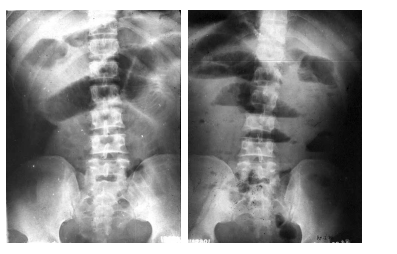

男性,47岁,(2月前因车祸行肠系膜裂伤修补术后反复阵发性腹痛1月余,加重2天,无放射性痛,伴少许腹胀,无恶心、呕吐,有肛门排气、排便。立位X线平片)见下图,该人可能是哪种疾病?

粘连性肠梗阻。